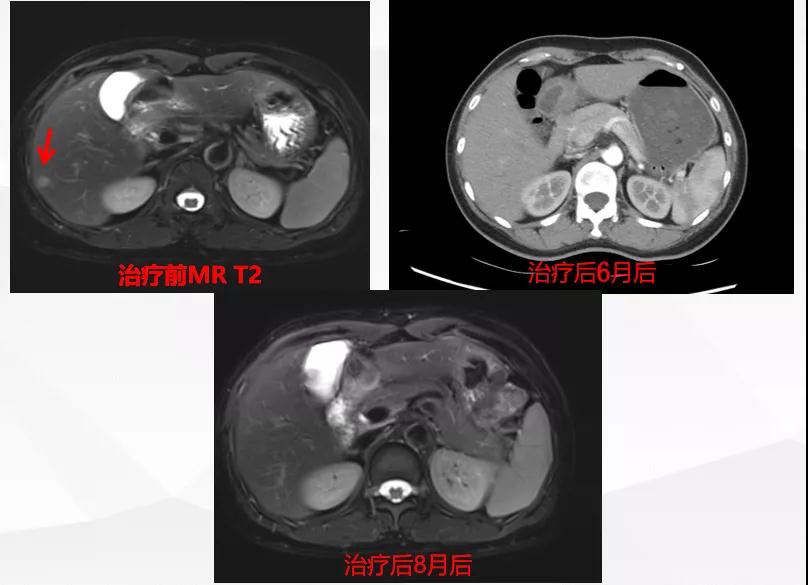

给予T-DM1治疗。治疗6个月后复查MR显示脑、肝、骨转移瘤均较前明显缩小,达到部分缓解(PR)(图2)。目前PFS已达10+个月。

图2

患者为ⅢA期(cT3N1M0)、三阳性乳腺癌,经AC-TH新辅助治疗达到降期(ypT2N0M0)。患者内分泌+抗HER2辅助治疗结束6个月时出现转移进展(脑、肝、骨),给予THP一线治疗,因无法耐受毒副作用而改为T-DM1,治疗6个月达到肝、脑、骨转移PR,患者目前中位PFS已超过10个月,T-DM1治疗过程中仅出现轻度CIT,且可自行恢复。